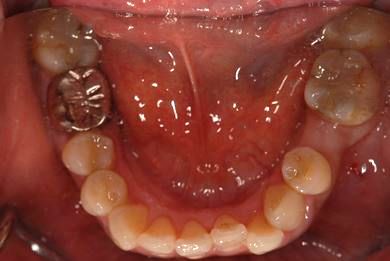

| 性別/年齢 | 女性 / 45歳 | ||||||||||||||||||||||||||||||||

| 主訴 | 以前治療した歯の歯ぐきから出膿。他の歯科でインプラントかブリッジしか方法がないが、骨の状態からインプラント治療は無理かもしれないと言われたことに不安を感じ、セカンドオピニオンを求めて来院。 | ||||||||||||||||||||||||||||||||

| 治療方針 | 保存不能の歯を抜歯し、インプラント治療にて機能的・審美的回復を行う。 | ||||||||||||||||||||||||||||||||

| 治療内容 | インプラント1本、ハイブリッドセラミッククラウン1本 | ||||||||||||||||||||||||||||||||

| 総治療費 | 310,905円 | ||||||||||||||||||||||||||||||||

| 治療期間 | 5ヶ月 |